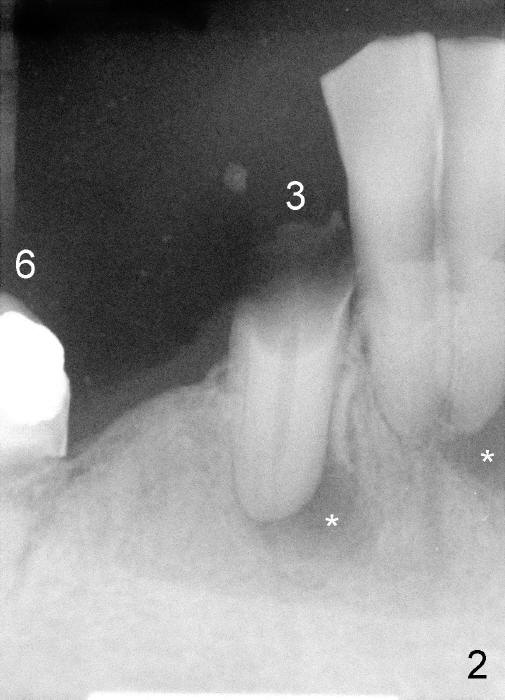

Several months ago, Philip (77 years old) was receiving chemotherapy for bladder cancer.  His lower right bridge broke down (Fig.1,2: #3-6: from canine to first molar).  The two abutment teeth (#3, 6) are nonsalvageable (Fig.4).  Ideally, immediate implant should be placed and implant-supported bridge is to be made.  The ridge at the site of #4 and 5 (premolars) is narrow.

Four months later, he returns and asks for implant restoration.  The ridge at the site of #3 is quite narrow (Fig.5).  While the socket of #3 is radiolucent (Fig.3 * under #3), there is an periapical abscess of the neighboring tooth (separate *).  It appears unsafe to place an implant at the site of #3, although anesthetic has been injected (Fig.5 *).  Instead an implant is placed at the site of #6 (5x14), further away from the infection.